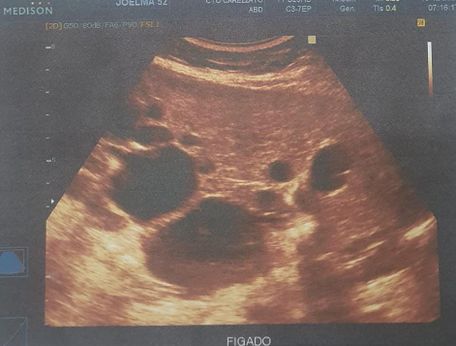

Foi realizado exame de imagem (21/10/2024), ultrassonografia abdominal com os seguintes achados (figura 1.1, 1.2, 2 e 3) Exames laboratoriais (21/10/2024): Acido úrico 2 mg/dl, Bilirrubina total 0,37 mg/dl, Bilirrubina direta 0,18 mg/dl, Bilirrubina indireta 0,19 mg/dl, TGP 21 u/l, TGO 16 U/L, Uréia 34 mg/dl, Creatinina 0,51 mg/dl, Sorologia para hepatite B, C não reagente.

Figura 1.1 e 1.2: identificando fígado de contornos irregulares, parênquima heterogêneo, ecogenicidade aumentada, trama vascular diminuída e volume aumentado, múltiplos cistos no parênquima hepático, o maior no lobo esquerdo medindo 8.9 cm x 7.0 cm.